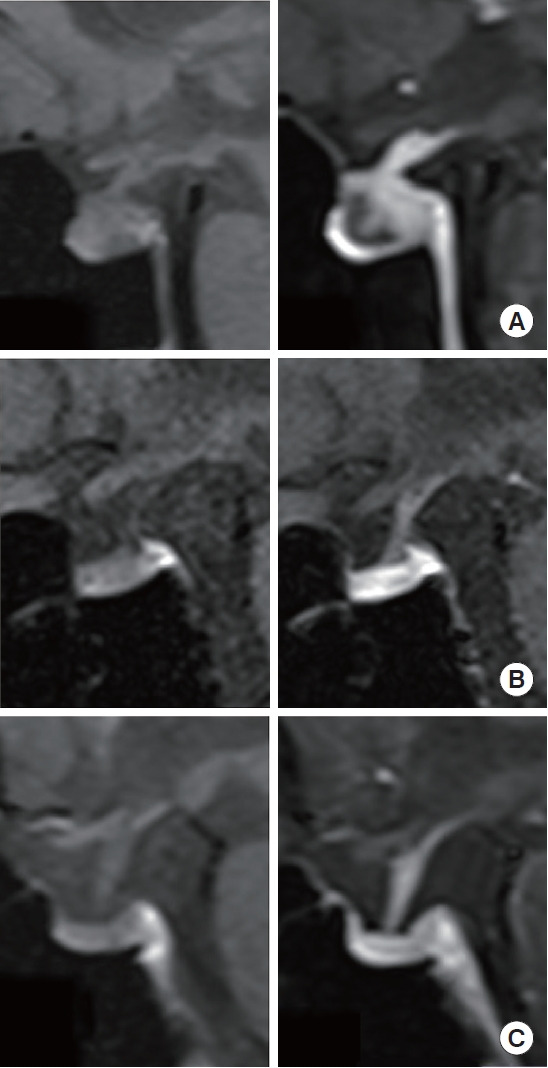

Results: PD-1/CTLA-4-Abs therapy showed higher incidence rates of pituitary irAEs (16/74 [21.6%] vs. 25/748 [3.3%], P<0.001), Multi-D (9/74 [12.2%] vs. 2/748 [0.3%], P<0.001), and IAD (7/74 [9.5%] vs. 23/748 [3.1%], P=0.014) than PD-1-Ab monotherapy. ACTH deficiency was observed in all cases, whereas the prevalence rates of luteinizing hormone deficiency (8/16 [50.0%] vs. 1/25 [4.0%]), follicle-stimulating hormone deficiency (6/16 [37.5%] vs. 1/25 [4.0%]), and thyrotropin deficiency (4/16 [25.0%] vs. 0/25 [0%]) were significantly higher after PD-1/CTLA-4-Abs than after PD-1-Ab treatment. Pituitary enlargement, which was observed only in the Multi-D cases, was significantly more frequent after PD-1/CTLA-4-Abs than after PD-1-Ab treatment (6/16 [37.5%] vs. 0/25 [0%], P=0.002).